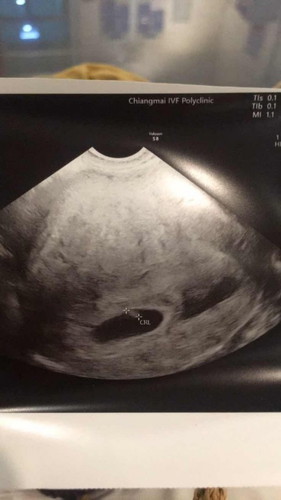

เมื่อวานไปอัตราซาวตามหมอนัด 6w 2d ผ่านช่องคลอด เจอสัญณานชีพน้อง แต่ปรากฏว่า หมอเจอแอ่งเลือด ข้างๆน้อง แม่ๆท่านไหนเคยเป็นบ้างคะ